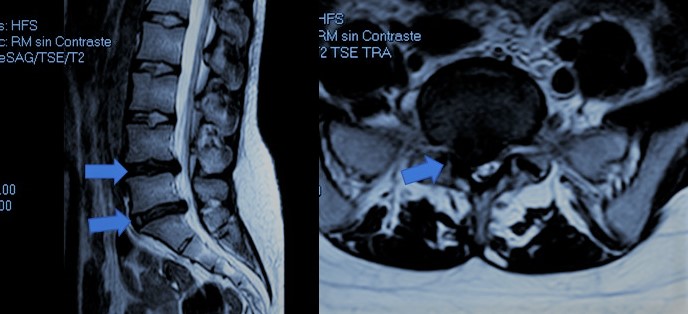

Especialista en el tratamiento de la hernia discal en Almería

Conozca el tratamiento de la hernia discal mediante microcirugía